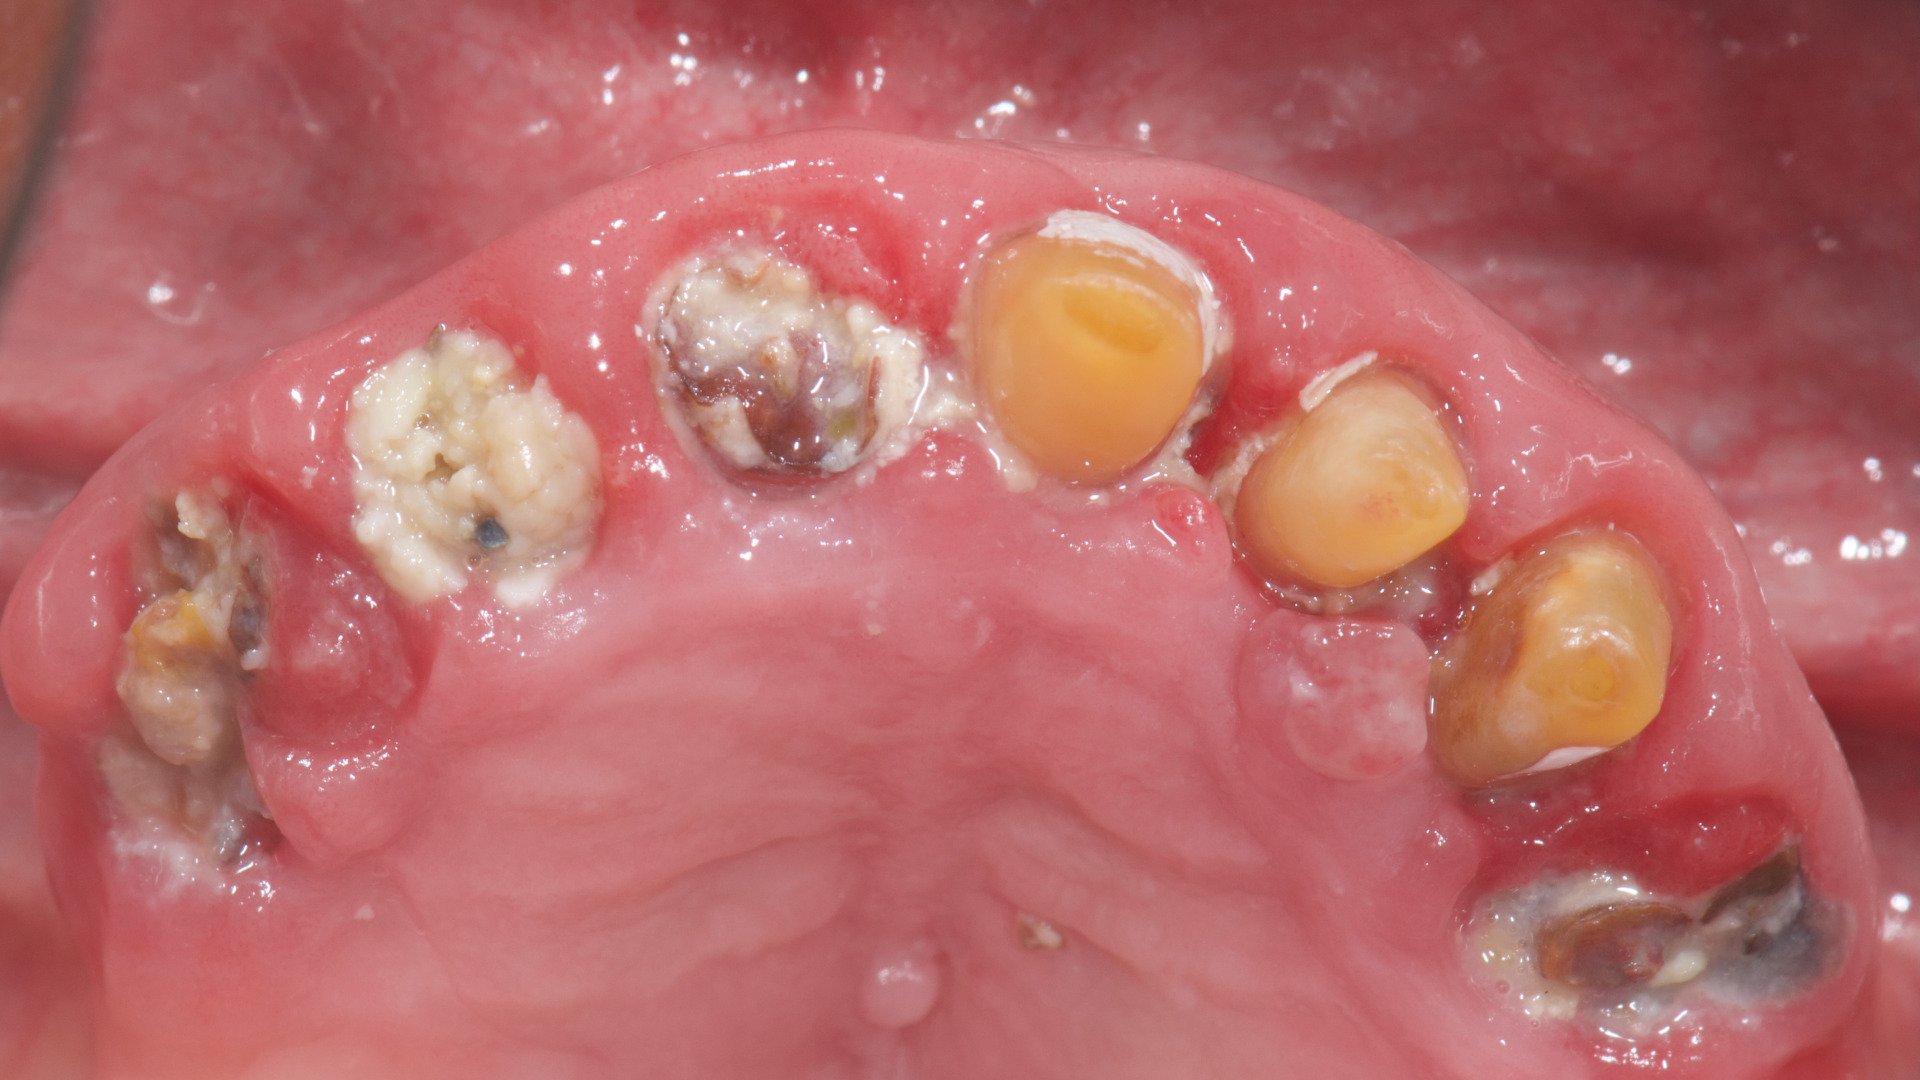

Fig. 2: Initial situation, occlusal view.

An 85-year-old partially edentulous patient was referred to our clinic for full-arch rehabilitation of the maxilla. The patient was in good general health and a non-smoker. His primary complaints included difficulty in chewing, maxillary pain and occasional halitosis. Clinical and radiographic evaluation revealed a short-span fixed metal–ceramic prosthesis supported by seven anterior maxillary teeth. The prosthesis had debonded, and four of the abutment teeth were structurally compromised. The remaining three showed varying degrees of caries and periodontal problems. A diagnosis of failing dentition was established (Figs. 1 & 2).